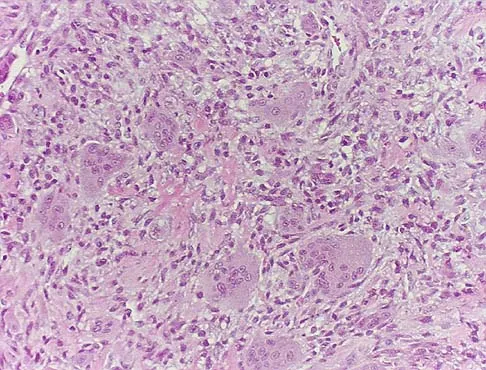

A 69-year-old man has a painful slow-growing lesion of the distal phalanx of his thumb. History reveals that he has had chronic osteomyelitis of the thumb for the past 12 years. The radiograph and biopsy specimens are seen in Figures 9a through 9c. Treatment should consist of

The diagnosis is squamous cell carcinoma. The radiograph shows a destructive lesion, and the histologic slides demonstrate squamous cells invading bone. The preferred treatment for squamous cell carcinoma is wide resection; however, in this location a wide margin can be achieved only with amputation. Overall survival in patients with squamous cell carcinoma secondary to chronic osteomyelitis is not significantly worse than that expected for age-matched controls. Dell PC: Hand, in Simon MA, Springfield D (eds): Surgery for Bone and Soft Tissue Tumors. Philadelphia, PA, Lippincott-Raven, 1998, pp 405-420.